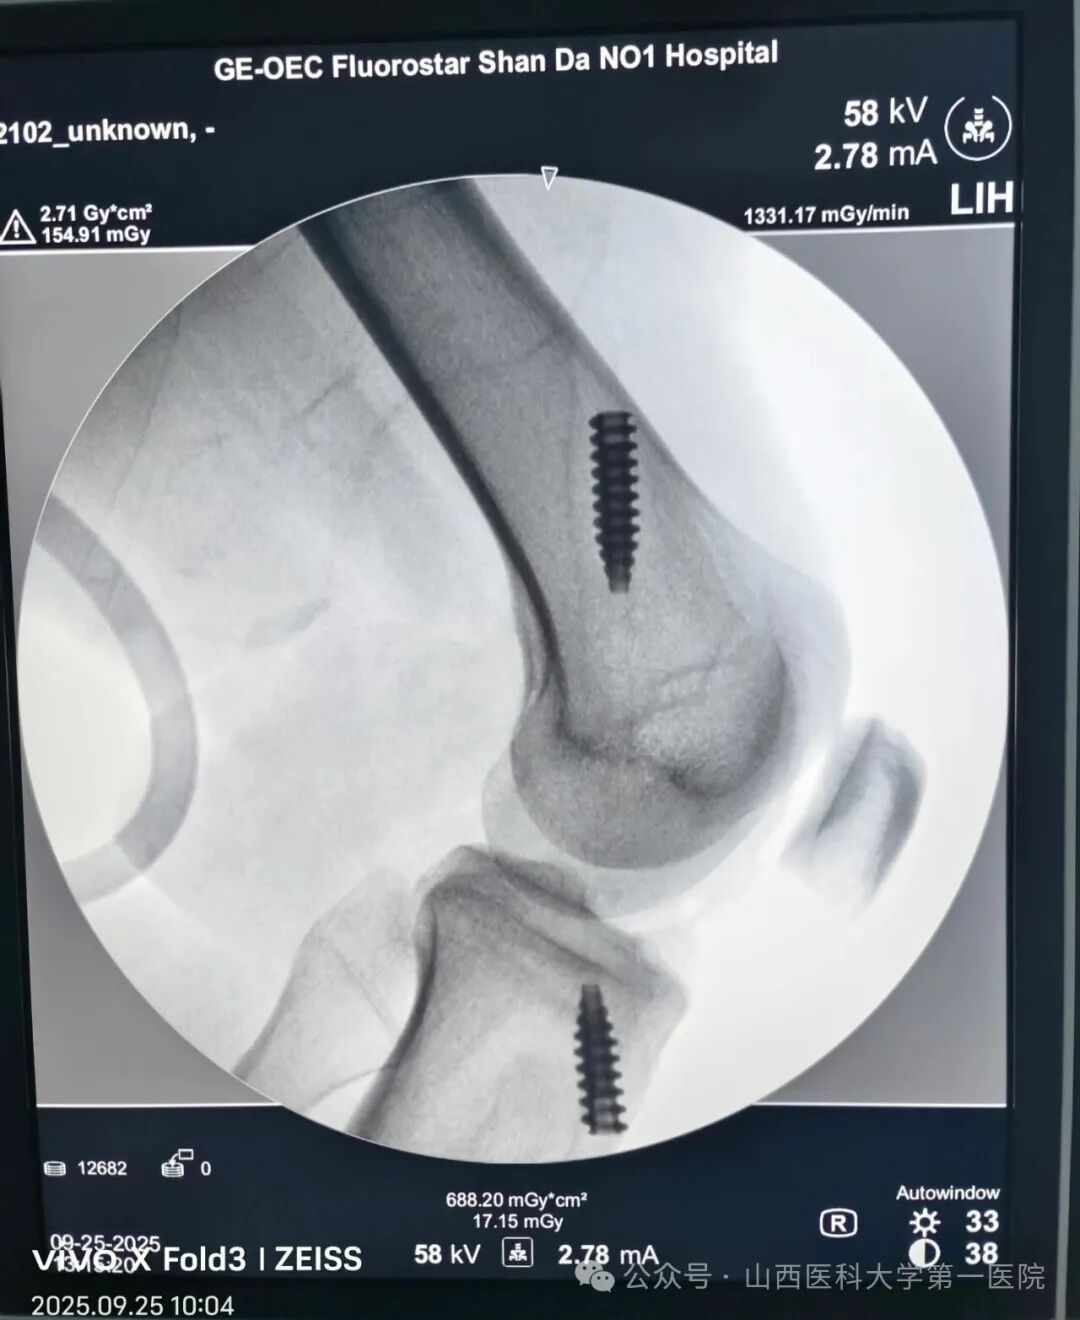

在完善术前检查和麻醉评估后,医生开始实施手术,术中采用人工韧带对其损伤的交叉韧带进行重建(人工韧带的强度约是自体韧带的3.2倍),术后即可开始康复锻炼,有利于肌肉和关节功能的尽早康复。手术历时1小时40分钟,患者术后2小时饮水、进食并开始踝泵运动,26日早7:00下床活动,经评估于上午9点顺利出院。这是骨科运动医学专业与日间手术中心的又一次完美合作,再度扩展了日间手术范畴,提升了日间手术的病种质量。